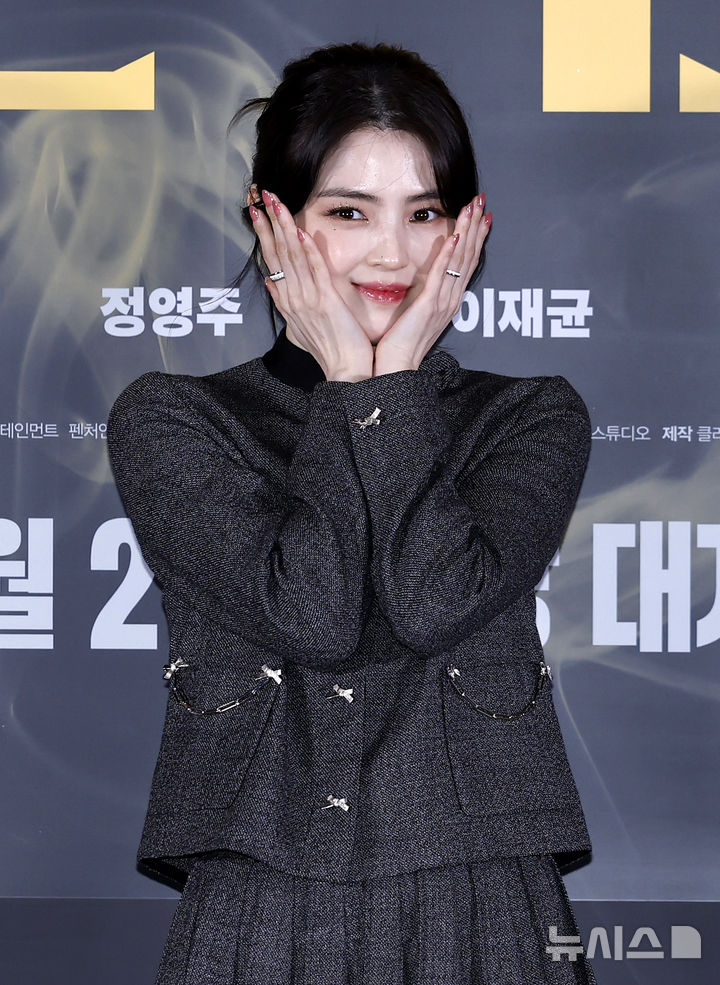

![[서울=뉴시스] 소말리아에 거주 중인 익명의 24세 여성은 지난 11월 소말리아 모가디슈 인근에 있는 자택에서 지붕을 뚫고 날아든 총알에 피격당했다. 사진은 의료진이 공개한 여성의 컴퓨터단층촬영(CT) 사진. (사진=국제수술사례보고서저널) 2023.04.28. *재판매 및 DB 금지](https://img1.newsis.com/2023/04/28/NISI20230428_0001254264_web.jpg?rnd=20230428162627)

[서울=뉴시스] 소말리아에 거주 중인 익명의 24세 여성은 지난 11월 소말리아 모가디슈 인근에 있는 자택에서 지붕을 뚫고 날아든 총알에 피격당했다. 사진은 의료진이 공개한 여성의 컴퓨터단층촬영(CT) 사진. (사진=국제수술사례보고서저널) 2023.04.28. *재판매 및 DB 금지

26일(현지시간) 영국 데일리스타에 따르면 익명의 24세 여성은 지난 11월 소말리아 모가디슈 인근에 있는 자택에서 휴식을 취하던 와중 난데없이 총알에 피격당했다.

지붕을 뚫고 날아든 총알에 맞은 여성은 소말리아 모가디슈에 있는 에르도안 병원으로 이송돼 수술대에 올랐다. 수술 보고서에 따르면 가랑이 사이로 파고든 총알은 정확하게 여성의 생식기에 박힌 채였다.

에르도안 병원 관계자는 수술 보고서를 통해 "우리가 아는 한 이번 사례는 여성의 외음부를 관통해 음핵에 박힌 첫 번째 탄환 사례이다"라고 밝혔다. 해당 보고서는 '국제수술사례보고서저널'에 등재됐다.

총알이 박힌 여성은 국소 마취제를 투여받은 이후 총알 제거 수술을 받았다. 수술을 집도한 의료진은 총알이 느린 속도로 날아와 다행히 부상이 심하지 않았다고 밝혔다. 여성은 수술일 바로 다음 날 1달 후에 있을 예후 진찰 예약을 잡은 후 건강한 상태로 퇴원한 것으로 알려졌다.